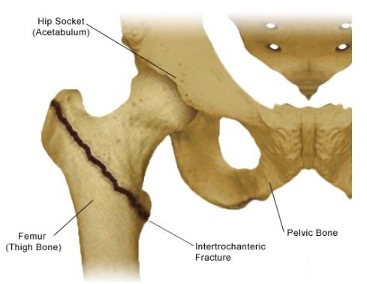

- Intertrochanteric Hip Fracture – A break in the femur where it makes a turn from the long thigh bone to the hip, known as an intertrochanteric fracture. These are successfully treated with fixation and rarely need replacement.

Intertrochanteric fractures occur in the area positioned below the femoral neck, between both greater and lesser trochanters. Fortunately, two viable treatment forms are available: a sliding compression hip screw combined with a side plate or an intramedullary nail.

- Treatment With A Compression Screw & Side Plate – The outer side of the bone is secured by a compression hip screw, allowing impaction and compression to take place at the fracture site, drastically increasing stability and aiding in recovery. A lag screw is placed through the plate into the femoral head and neck for additional reinforcement. Older, rarely indicated in today’s algorithm.

- Treatment With A Intramedullary Nail – To stabilize the femoral head, an intramedullary nail is inserted directly into the marrow canal of the bone through drilling on top of the greater trochanter. Subsequently, one or more screws are drilled through this insertion and fastened tightly to secure it. Newer and more current.